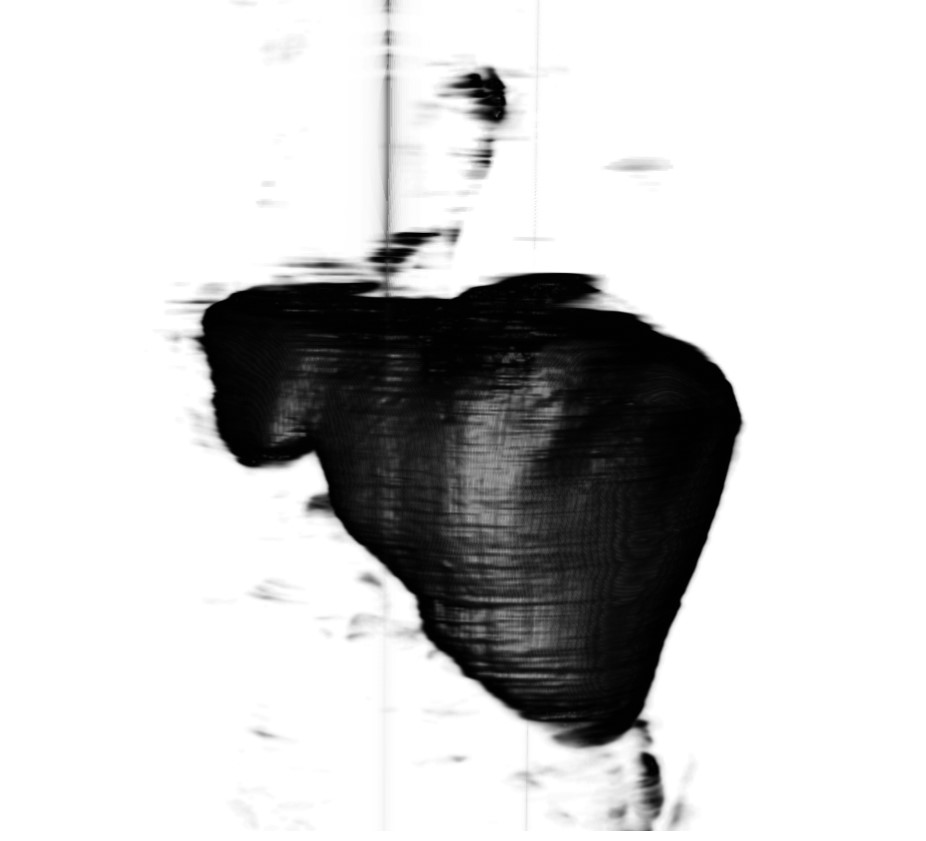

We have experimented with different values for the parameter: seemed to be too small as it could not separate a minimum of the required relevant features in the image, while starting with , the result image started to be too fragmented feature-wise. The 2D result for is presented in Figure 3.1. We also tried this algorithm in 3D on a CT volume for , as shown in Figure 3.2.

As it can be seen in the Figures 3.1 and 3.2, because the algorithm uses the pixels’ or voxel’s luminance levels to decide to which class each pixel belongs, and because multiple anatomical structures can have similar HU levels, this algorithm can not be used as such for the task of liver segmentation without any human intervention.